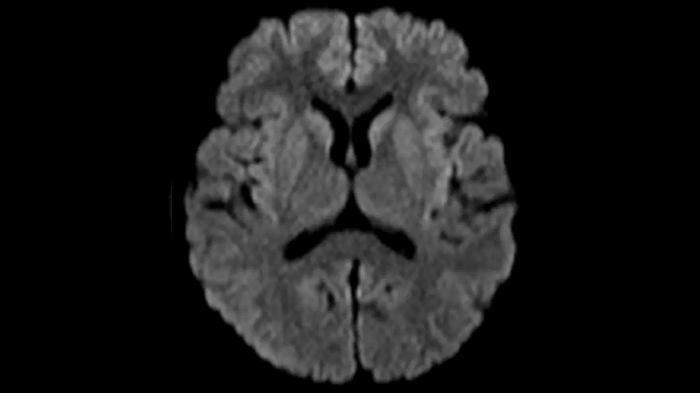

DWI b1000

Exceptional diffusion-weighted imaging with MAGNETOM Free.Star.

PAT 2

0.7 x 0.7 x 5.0 mm2

TA 2:53 minutes

MAC-ID: 7aaaa0195. Image Credit: Siemens Healthineers